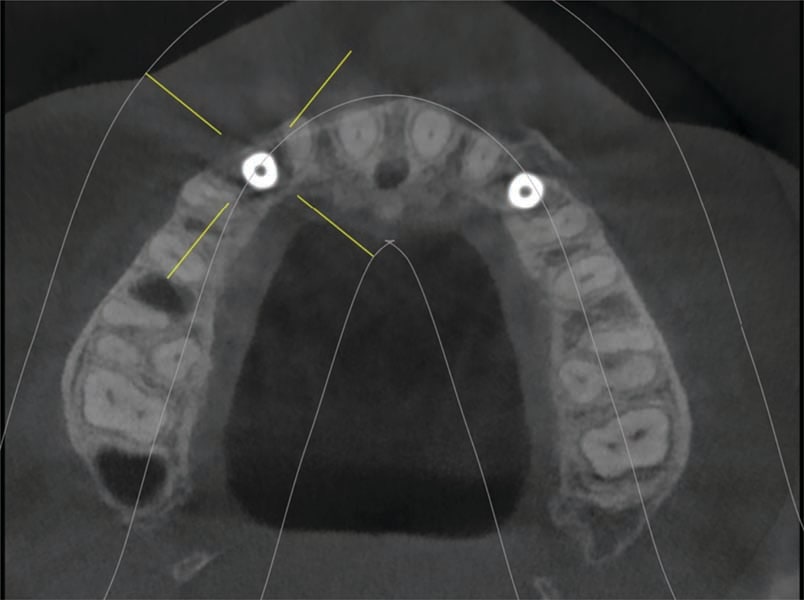

The oral surgeon, Dr. Defalco, saw the patient, and a CBCT was taken. Cross-sectional views at 6 and 11 noted a narrow ridge width due to a concavity at both sites related to lack of the permanent canines (Figure 5). Minimal roots were present for the deciduous canines (teeth C and I). Insufficient ridge width was present at either site to permit implant placement without site grafting to eliminate the facial ridge concavity. Block grafting of the sites at the time of extraction was recommended, and following site healing and graft conversion to the host ridges implants could be placed.

The grafts were allowed to heal for 6 months (Figure 10 through Figure 12). A CBCT was taken to evaluate the ridge width at the grafted sites. Analysis determined adequate ridge width was now present to allow implant placement. The patient presented to Dr. Puccio and Dr. Defalco for placement at sites 6 and 11. Consent forms were reviewed with the patient and signed. Local anesthetic was administered and a full thickness flap elevated to expose the fixation screw on the facial aspect of the ridge that had been placed to secure the block grafts. The screw was removed from both sites. A surgical guide (fabricated in a similar fashion as discussed above) was inserted intraorally, and osteotomies were created after fixation screws were removed at sites 6 and 11. A 3.6-by-11-mm EV Profile implant (Astra Tech) was placed at each site. Cover screws were placed and the flap secured with sutures. The patient returned at 2 weeks post implant placement. Healing appeared uneventful, and the patient was scheduled for a recall prophy.